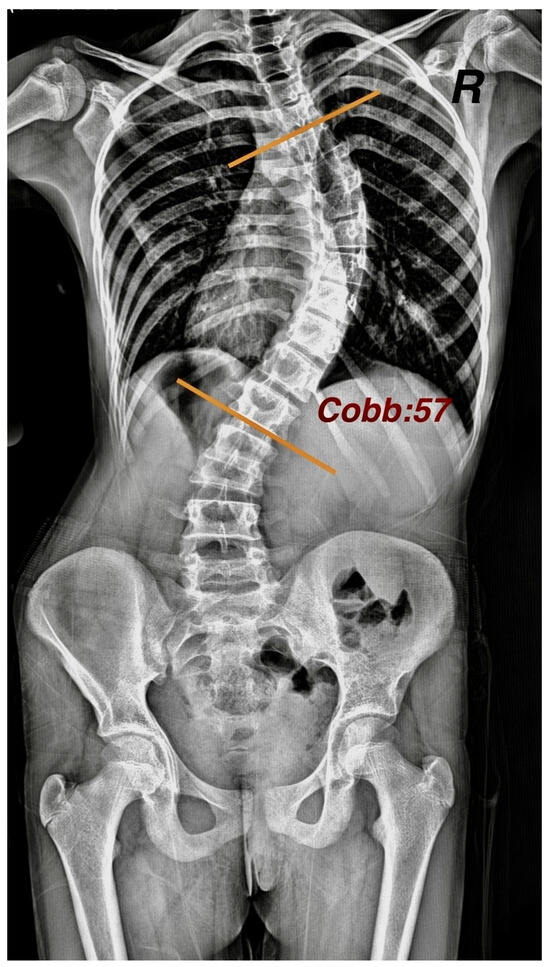

The Cobb angle was calculated in degrees by a specialist orthopedist on a latest spine posteroanterior (PA) radiograph from an archive of individuals in the standing position (Figure 2).

For the Cobb angle measurement, tangents were drawn from the upper limit of the uppermost vertebra included in the curvature and from the lower limit of the lowest vertebra. The angle formed at the intersection of these lines was recorded as the Cobb angle. As scoliosis is clinically defined by a spinal curvature greater than 10°, and no treatment is administered for curves below this threshold in the study clinic, only patients with a Cobb angle exceeding 10° were included.

Figure 2. Measurement of Cobb angle on posteroanterior radiograph.